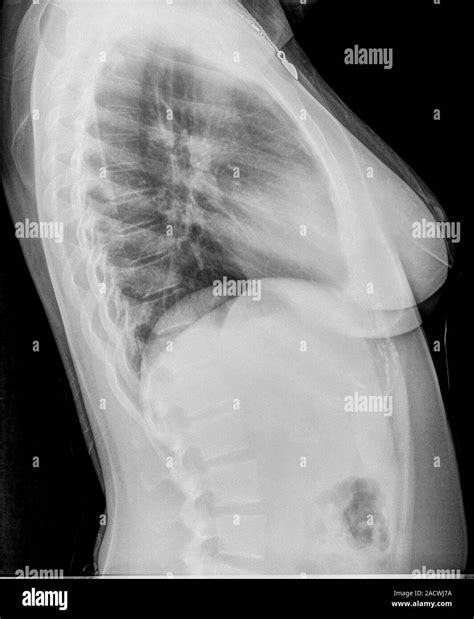

A bronchitis X ray is a crucial diagnostic tool that helps healthcare providers visualize the lungs and bronchial tubes. This imaging technique uses X-rays to create detailed images of the chest, allowing doctors to identify any abnormalities or inflammation. The bronchitis X ray can reveal:

• Inflammation and swelling of the bronchial tubes

• Presence of mucus or fluid in the lungs

• Signs of infection or pneumonia

• Structural abnormalities in the lungs

During the procedure, the patient will be asked to stand or sit in front of an X-ray machine. The technician will position the patient to ensure the best possible images are captured. The patient may be asked to hold their breath briefly while the X-ray is taken to minimize movement and ensure clarity.

Interpreting Bronchitis X Ray Results

Interpreting the results of a bronchitis X ray requires the expertise of a radiologist or healthcare provider. The images are carefully examined for signs of inflammation, infection, or other abnormalities. Key findings that may be noted include:

• Increased density or opacity in the lungs, indicating inflammation or fluid buildup

• Thickening of the bronchial walls

• Presence of nodules or masses

• Signs of pneumonia or other respiratory infections